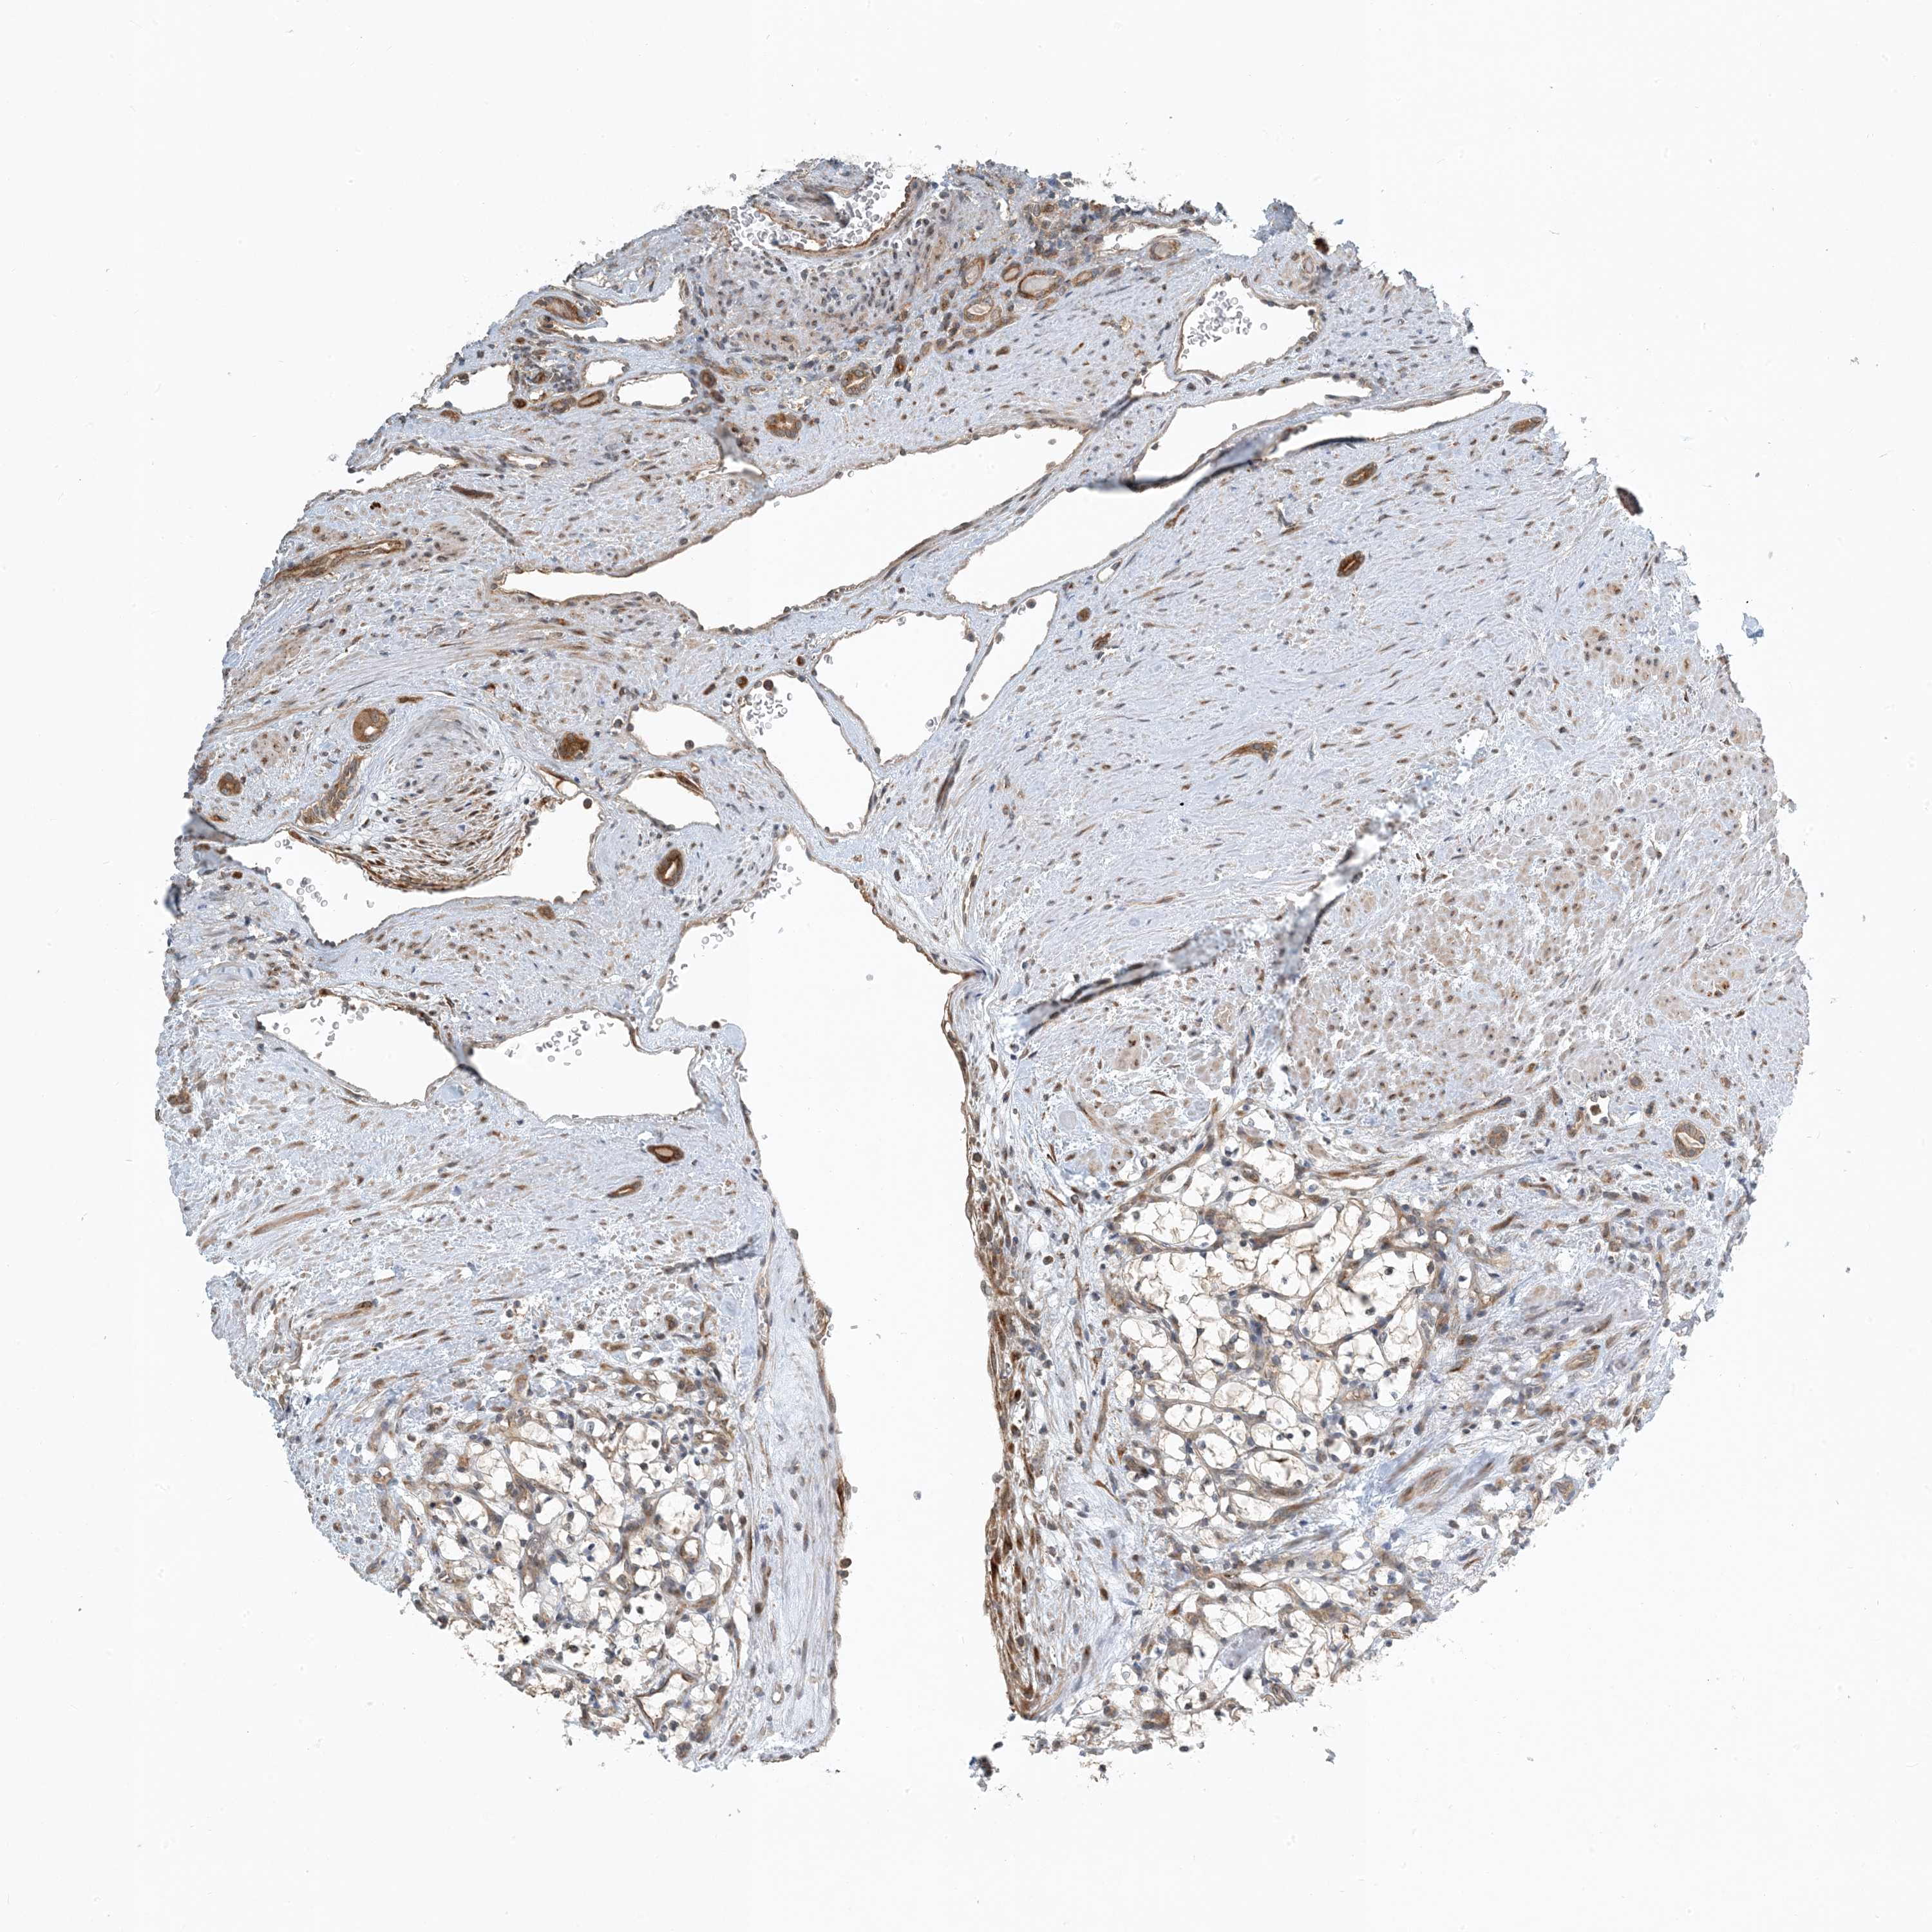

TCGA RNA samplesi

RNA-seq data is reported as average FPKM (number Fragments Per Kilobase of exon per Million reads), generated by the The Cancer Genome Atlas (TCGA) .

Normal distribution across the dataset is visualized with box plots, shown as median and 25th and 75th percentiles. Points are displayed as outliers if they are above or below 1.5 times the interquartile range. FPKM values of the individual samples are presented next to the box plot.

Average pTPM 2.5

Number of samples 100